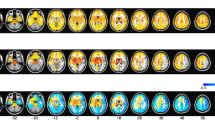

BOLD signal in swallowing tasks in general linear model and independent component analyses. (A) In GLM analyses, significant BOLD signals were seen in both the lateral precentral gyri, postcentral gyri, anterior insular cortices, supramarginal gyri, pre-SMA, thalami, and visual cortices. (B) IC 17 showed the strongest positive correlation with BOLD signal (r = 0.64, p < 0.001) in the swallowing task in both the lateral precentral gyri, postcentral gyri, anterior insular cortices, supramarginal gyri, pre-SMA, and anterior cingulate gyri. GLM, general linear model; BOLD, blood oxygen level-dependent; SMA, supplementary motor area; IC, independent component; FWE, family-wise error.

During swallowing tasks, significant BOLD activation was observed in both the inferior pericentral gyri, supramarginal gyri, anterior insular cortices, pre-supplementary motor area (pre-SMA), and visual cortices in the GLM analysis (Fig. 1A). The BOLD activation in the swallowing task contrasted with that in the non-swallowing task revealed dominant activity in the areas of both the lateral precentral gyri, postcentral gyri, supramarginal gyri, pre-SMA, and right thalamus, and showed a more spatially localized pattern than that in the swallowing task without contrast (Fig. 2).

Among the 26 independent components (ICs), 12 were positively correlated with the swallowing task. IC 17 had the strongest positive correlation with BOLD activation (r = 0.64, p < 0.001) during the swallowing task in both the lateral precentral gyri, postcentral gyri, supramarginal gyri, anterior insular cortices, pre-SMA, and anterior cingulate gyri (Fig. 1B).